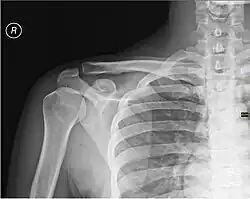

Скелет

Каркасом плеча служит плечевая кость.

При травмах плеча возможно повреждение нервов и сосудов, а также переломы плечевой кости, наиболее частой локализацией которых является шейка плечевой кости[1].